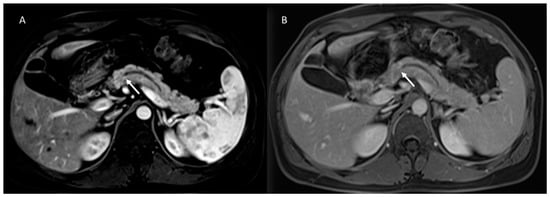

- Granata, V.; Grassi, R.; Fusco, R.; Galdiero, R.; Setola, S.V.; Palaia, R.; Belli, A.; Silvestro, L.; Cozzi, D.; Brunese, L.; et al. Pancreatic cancer detection and characterization: State of the art and radiomics. Eur. Rev. Med. Pharmacol. Sci. 2021, 25, 3684–3699. [Google Scholar] [CrossRef] [PubMed]

- Granata, V.; Fusco, R.; Sansone, M.; Grassi, R.; Maio, F.; Palaia, R.; Tatangelo, F.; Botti, G.; Grimm, R.; Curley, S.; et al. Magnetic resonance imaging in the assessment of pancreatic cancer with quantitative parameter extraction by means of dynamic contrast-enhanced magnetic resonance imaging, diffusion kurtosis imaging and intravoxel incoherent motion diffusion-weighted imaging. Ther. Adv. Gastroenterol. 2020, 13, 1756284819885052. [Google Scholar] [CrossRef]